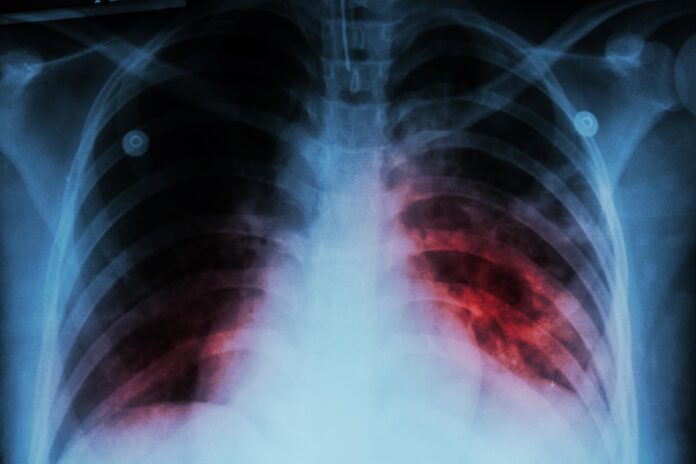

Sonora. — Sonora registra mil 322 casos de tuberculosis respiratoria en este 2025, y Hermosillo concentra más de la mitad, con el 51.2% del total, de acuerdo con el Sistema Único de Información para la Vigilancia Epidemiológica (Suive) de la Secretaría de Salud.

Ante el caso confirmado de tuberculosis de una estudiante de la Universidad de Sonora, el infectólogo Dr. Alejandro González Mares advirtió que Sonora es el segundo estado a nivel nacional con la tasa más alta de casos de tuberculosis por habitante.